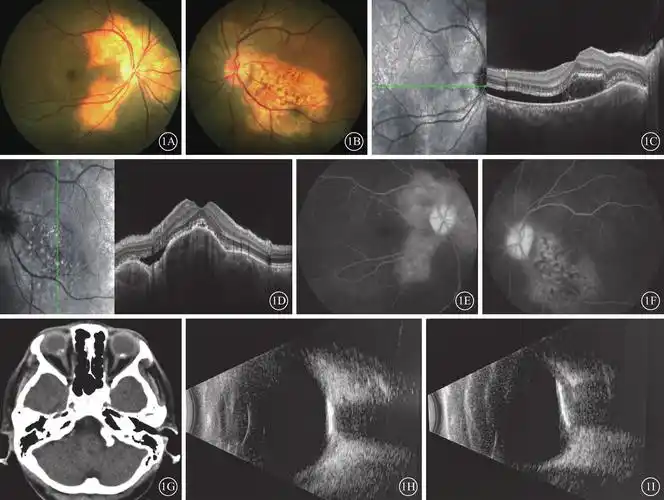

脉络膜骨瘤多种眼底影像特征对比观察

脉络膜骨瘤